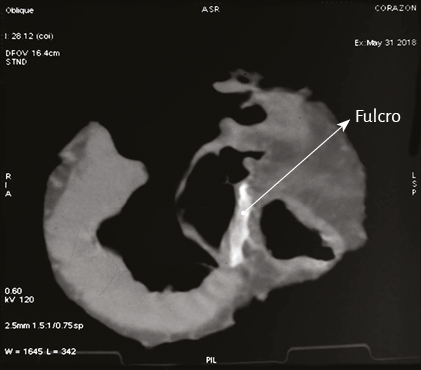

En bóvidos, la consistencia del fulcro cardíaco, óseo a la palpación (figuras 34 y 35), ha sido confirmada por la histología (figuras 36 a 38). Su tamaño, corroborado por disección (figura 39) y tomografía computada (figuras 58 y 59), es de aproximadamente 37 a 45 × 15 mm y de forma triangular. El análisis microscópico del fulcro cardíaco bovino muestra una matriz osteocondral trabecular con líneas segmentarias. Su estructura general asemeja al crecimiento metafisario de los huesos largos. A mayor aumento se pueden observar trabéculas óseas con osteoblastos y líneas segmentarias secundarias a aposición ósea. Los mismos hallazgos histológicos se han encontrado en chimpancés (109). La inserción secuencial de las fibras miocárdicas en el fulcro bovino se puede observar en las figuras 40-42.

Figura 58. Tomografía computada. Se evidencia imagen hiperdensa en la topografía del septum interventricular adyacente a la raíz de la aorta de aproximadamente 3,7 cm de longitud. Presenta una densidad de aproximadamente de 298 UH (corazón bovino).

Figura 59. Fulcro cardíaco en tomografía computada (corazón bovino).Al pie se muestra el fulcro resecado.

Imágenes del fulcro cardíaco. Los corazones de bovino, estudiados con tomografía computada (figuras 58-60), resonancia magnética (figuras 61 y 62) y radiología simple (figura 63) evidenciaron el núcleo osteo-condroide hallado en la disección, observándose la misma morfología y tamaño análogo. En la tomografía humana hemos encontrado, en el análisis de la región donde se encuentra el fulcro cardíaco a través de las disecciones realizadas, la presencia de una intensidad en unidades Hounsfield por encima de 110 UH, mientras que el músculo adyacente tiene unidades por debajo de 80 UH. De esta manera, en la imagen, la estructura del fulcro alcanza un promedio de 132 ± 4,5 HU. En las áreas adyacentes, correspondiente al músculo miocárdico, este valor se ubicó entre 47,96 ± 12,5 y 77,59 ± 21,64 HU (figura 64).